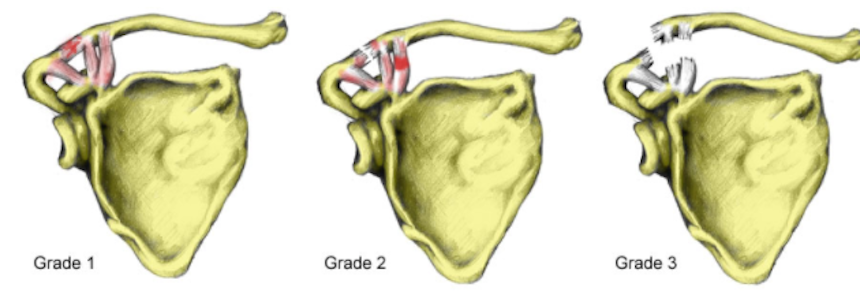

No se ha revelado si el serpentinero perdió el control de la motocicleta él sólo o si hubo un tercero involucrado. Lo que sí se sabe, es que el jugador estará un buen rato fuera pues el diagnóstico inicial es que sufrió un esguince de clavícula de grado dos. Es decir, hubo una separación en una articulación de la clavícula.